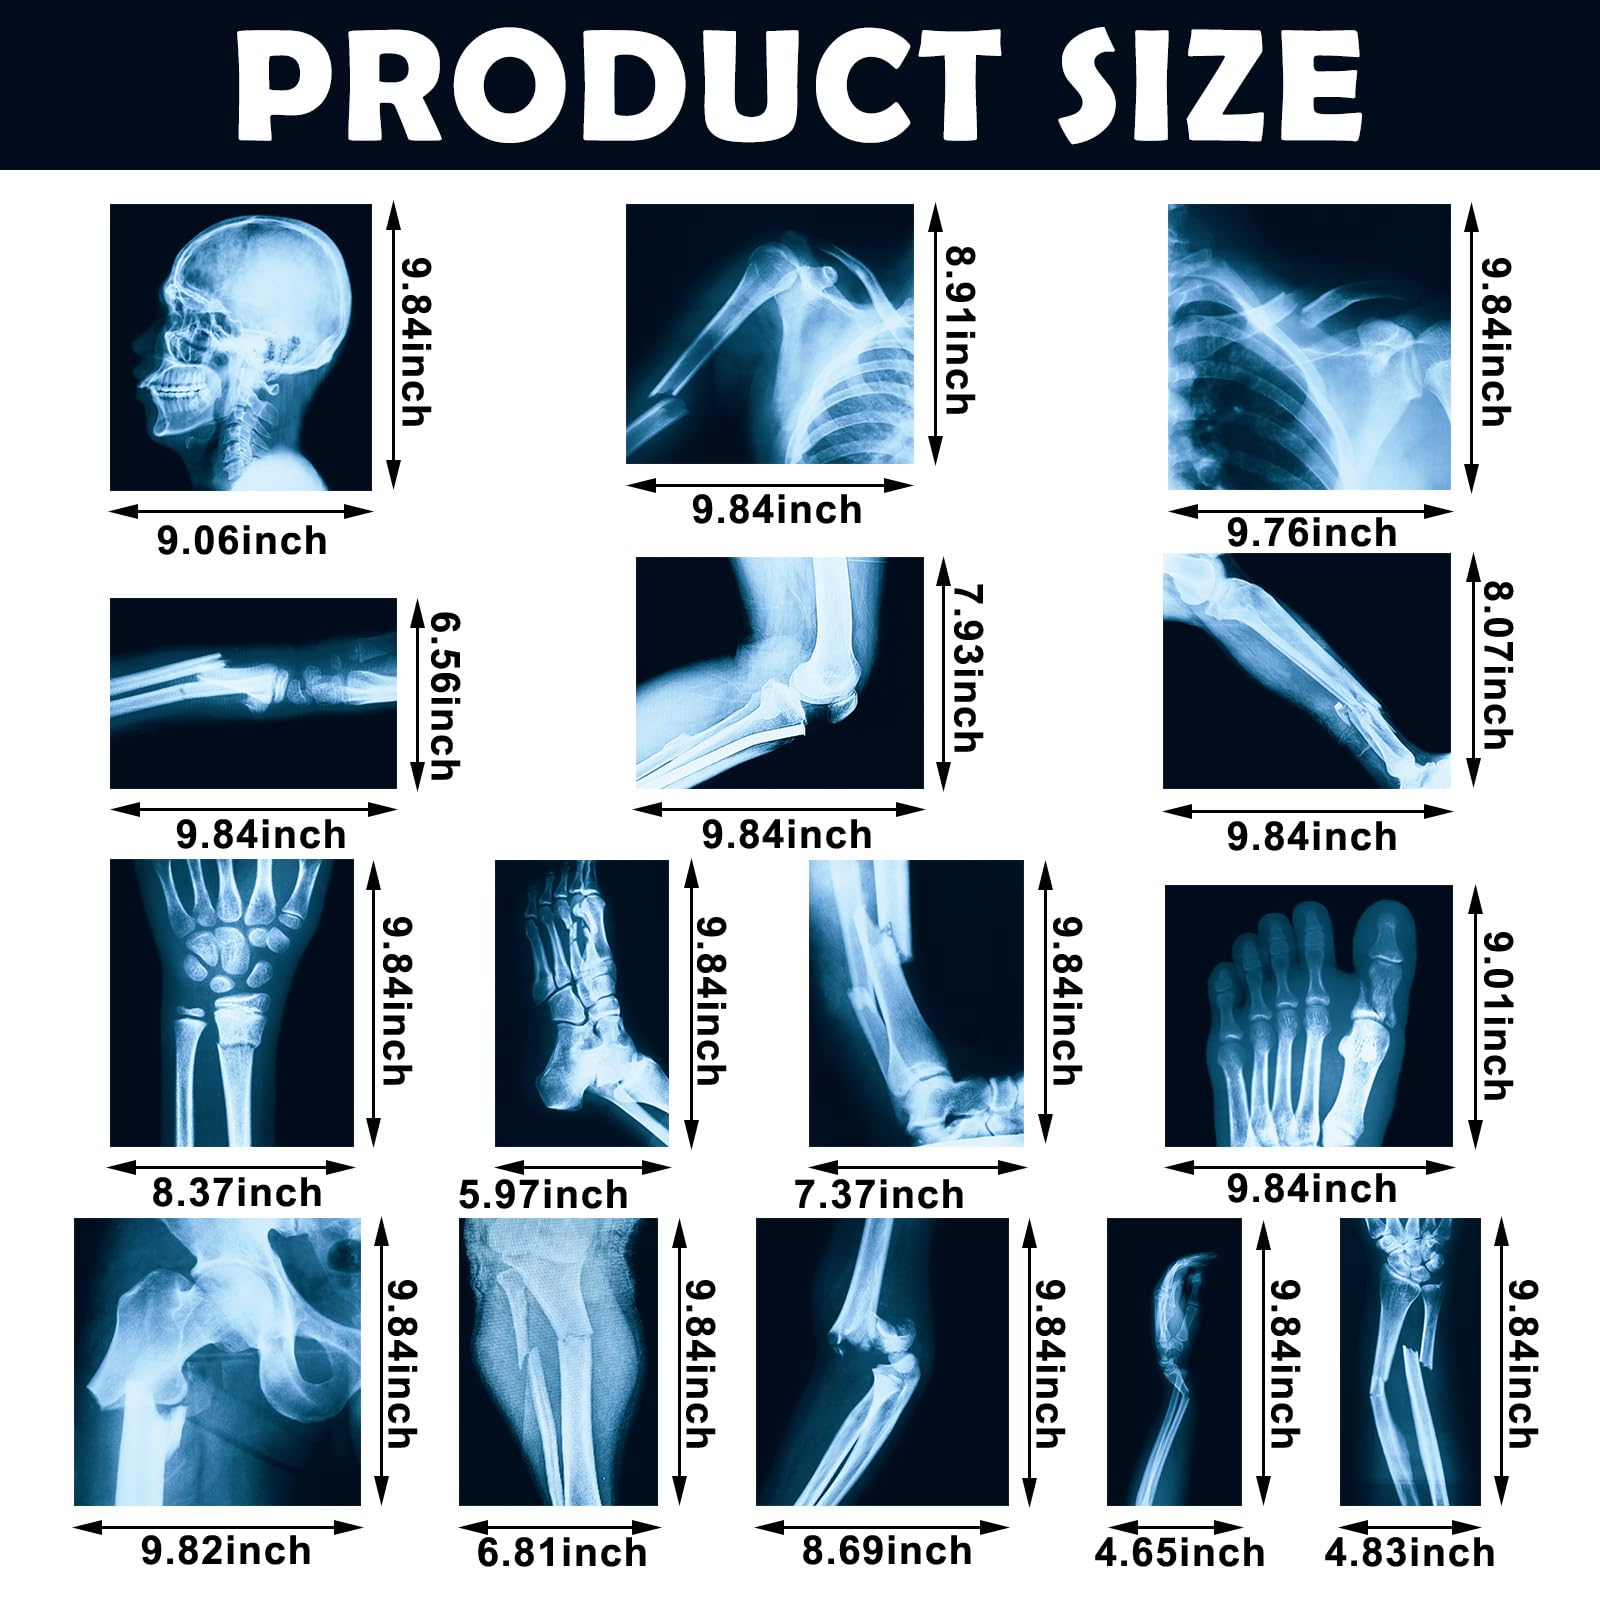

The 15 Pcs Broken Bones X Ray Set is an educational kit designed for children to explore and learn about human anatomy. Featuring 15 large, clear X-ray images of broken bones, this set is made from durable PVC plastic, ensuring safety and longevity. Perfect for classrooms or home use, it serves both educational and decorative purposes.